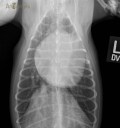

RadioQuiz 41: Hubert refuse même du poulet !

15 février 2019

RadioQuiz 40 – Sweetie a des métastases ?

30 septembre 2018

RadioQuiz 39 – Blondie passe au bistouri

1 juin 2018

RadioQuiz 38 – Igor montre les dents entre deux épisodes de vomissement !

30 novembre 2017

RadioQuiz 37 – Terre-Neuve en détresse !

2 février 2017

RadioQuiz 36 – Chat enveloppé cherche à faire pipi

24 août 2016

RadioQuiz 35 – Ouch !

6 mai 2016

RadioQuiz 34 – Un souffle depuis 4 ans

27 janvier 2016